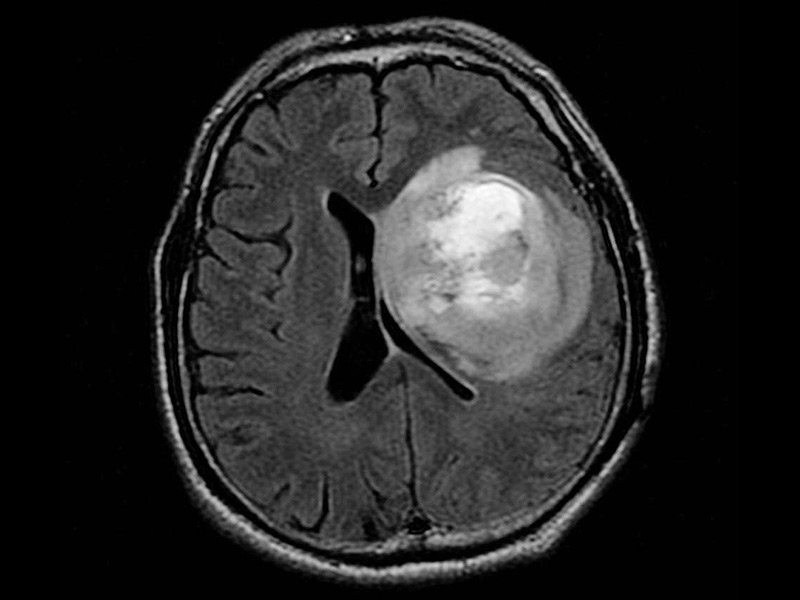

在大多数情况下,医生并不知道胶质母细胞瘤(GBM)的根本原因,对于其成因目前仍是未知的。胶质母细胞瘤的治疗具有挑战性,因为肿瘤以触手状扩散,难以全部切除。胶质母细...

胶质母细胞瘤属于高级别胶质瘤的一种,一般生长速度快,较易复发,预后较差。胶质母细胞瘤能活多久?INC巴特朗菲教授论文解析...